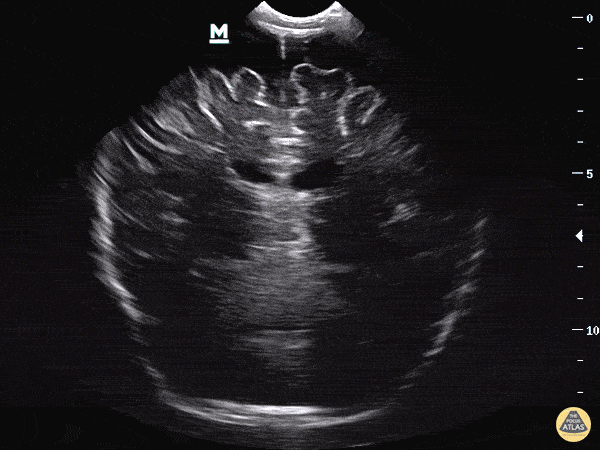

Extra-axial fluid overlying the superior portion of the frontal lobes in the patient from our blog post on the topic. 7 month old being followed by PCP for increasing head circumference, scheduled for outpatient MRI next week. Mother found patient was becoming somnolent with a full anterior fontanelle and brought the baby to the ER. POCUS performed immediately revealed unequal ventricle size, L>R, at which time neurosurgery was consulted, later CT, MRI performed as inpatient confirming obstructive hydrocephalus. Dr. Sathya Subramaniam - Childrens Hospital of Philadelphia Pediatric, EM Ultrasound